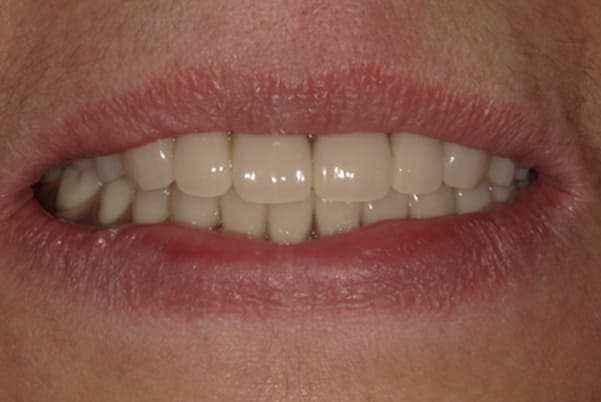

症例レポート[CASE.14]

上の歯を綺麗に治したい

- 性別・年齢

- 女性(50代)

- 主訴

- 上の歯を綺麗に治したい

- 治療

-

- 上顎ノンクラスプデンチャー

(チタン併用) - ジルコニアクラウン 9歯

- 治療期間

- 約7か月間

- 費用

- 上顎ノンクラスプデンチャー:33万円

(チタン併用) - ジルコニアクラウン:8.8万円×9歯

合計:112.2万円(税込)

左奥1本は虫歯で抜歯となりました。

歯がないところには、インプラント、ブリッジ、入れ歯の3つが選択肢となりますが、インプラントには抵抗がおありで、ブリッジの土台の奥歯は歯周病のため、できるだけ負担をかけたくないとのことで、最終的に入れ歯をご希望されました。

見える外側は金属がないバネを用い、見えない内側は違和感が小さく強度に優れ、入れ歯が安定するチタンを用いた部分入れ歯(特殊なノンクラスプデンチャー)

入れ歯では、犬歯にバネがかかりますが「入れ歯と分からないように」とのご希望で、外側のバネは審美性が高く、内側には強度が高く安定性がよく、また違和感が少ないチタンを併用したノンクラスプデンチャーで治療を行いました。

左上に入れ歯を装着されていますが、金属のバネがなく自然な口元に